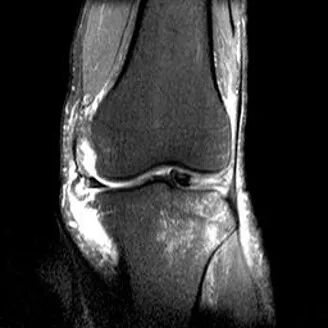

半月板撕裂定义与显示

1、半月板显示:以T2-WI加脂肪抑制为最好.2、半月板病变:最常见损伤是撕裂伤3、病因:慢性退变性撕裂和急性外伤性撕裂4、诊断方法:当半月板内出现线样高信号到达其游离缘或关节面时,即可诊断半月板撕裂5、病变信号变化:T1WI为线样稍高信号,T2(FS)或T2*WI信号更高6、半月板球形及线行高信号影未达关节面,为其慢性损伤或退行性改变(变性)7、MR诊断半月板撕裂的准确度达90-97%,特异性为94%,假阳性高于假阴性,主要是将膝横韧带与外侧半月板相邻的国肌腱鞘等误认为半月板撕裂.

半月板斜行撕裂

最常见类型:斜行撕裂表现为:在矢状面上见III级高信号到达半月板关节面的上缘或下缘